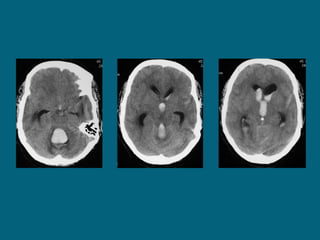

Intraventricular hemorrhage

ļ‚—Most commonly due to rupture of subependymal

vessels

ļ‚—Can occur from reflux of SAH or contiguous

extension of an intracerebral hemorrhage

ļ‚—Look for blood-cerebrospinal fluid level in occipital

horns